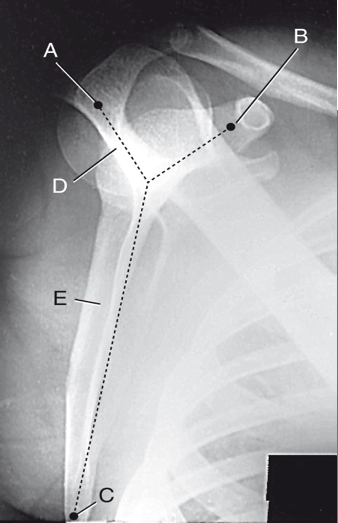

A

coracoid process

B

inferior angle

C

scapular spine

D

body of scapula

E

clavicle

glenoid fossa

acromion process

lesser tubercle

humeral head

F